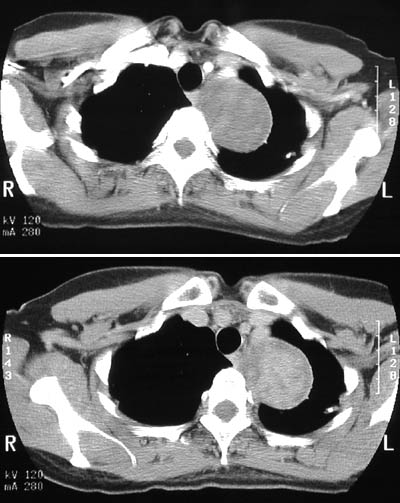

The large mass with discrete borders, seen in these views from a chest CT scan, is arising in the posterior mediastinum and extending into the thoracic inlet. This is a large schwannoma, a neoplasm arising from peripheral nerve sheath.